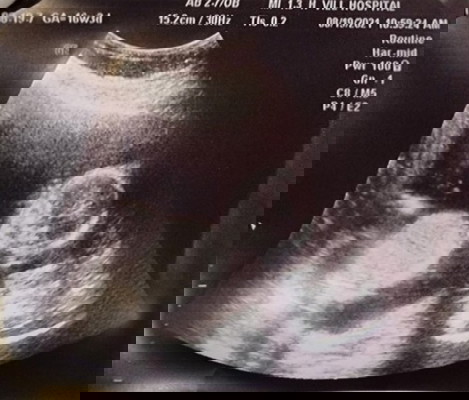

Boy or Girl?

Hi, #justforfun lang, currently #16weeks, ano kaya sa tingin nyo gender ni baby? Hehehe di pa makita kasi sa scan next month pa daw, naeexcite na ko hehehe. Again, for fun lang po hihi, I will surely still go back sa ultrasound next month for confirmation hehehe.